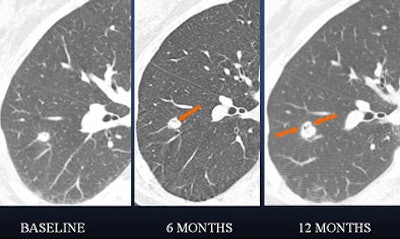

| In a 61-year-old woman a 6-mm nodule was found in the right lower lobe at baseline CT scan. At six-month follow-up, the nodule was determined to be stable in size. At 12 months, however, it had clearly grown in size. The nodule was biopsied and eventually diagnosed as adenocarcinoma. All images courtesy of Dr. Ann Leung. |

"If you look at the 12-month study (61-year-old woman, above), you will appreciate air lucency within that nodule," Leung said. "We're recognizing now as we are scrutinizing nodules much more carefully that the presence of air bronchograms is a concern for malignancy," she said. "If we look back at the first image, at six months, we can see that this lesion also had air bronchogram. We should have been more aggressive in trying to provide a diagnosis for this patient."